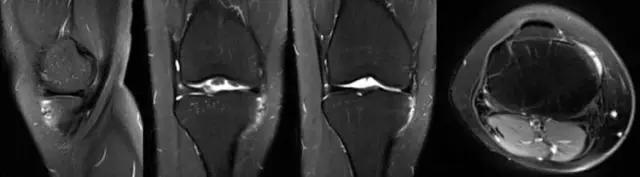

学习不是目的,使用才是目的!阅读MRI后,还应该说给病人听!怎样在病人面前说MRI? 下图为膝关节病损的早期-髌骨软化,MRI显示髌骨出现高信号。 这时应该告知病人:疾病怎么形成?有哪些表现?日常动作有什么影响?怎么治疗?今后病情如何发展?如何保护?

怎样在病人面前说MRI? 髌骨软化进一步发展-髌股关节炎,病情更重,MRI表现更重,股骨滑车也有改变;治疗效果也差。

怎样在病人面前说MRI? 结合解剖、生物力学、影响日常生活的主要症状-上楼梯、爬山疼痛明显,膝关节屈伸有弹响等讲给病人听,直接点到病人的“痛处”。说这些目的应该是为了治疗! 治疗-保守:理疗、关节内注射…… 手术:关节镜、人工关节……